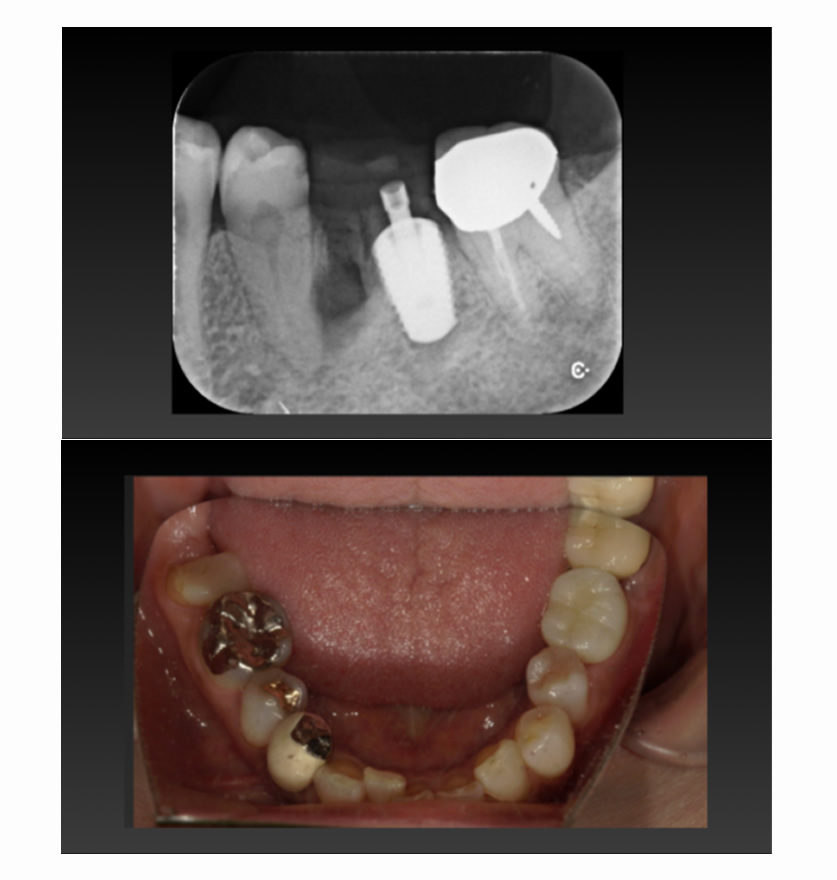

04 症例

04 右下の歯が割れ、左上が入れ歯なのでインプラント希望

Before

After

| 治療内容 | 右下の歯が割れている、左上が入れ歯なのでインプラント希望 |

| 患者さま | 50代男性 |

| 主訴 | 根が割れていて痛いのと、入れ歯の管理が大変なのでインプラントにしたい。 |

| 治療期間(目安) | 3ヶ月 |

| 治療費(税込:目安) | ¥984,500 |

| リスク | 術後に多少の痛みや腫れが出ることがある。歯肉退縮がおきると、歯と歯肉の間に隙間が生じることがあります。 |